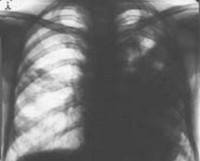

Картина, выявляемая по данным рентгенографии легких, различается в зависимости от формы бактериальной деструкции легких. В типичных случаях легочные деструкции определяются в виде полостей с горизонтальным уровнем жидкости, вокруг которых распространяется воспалительная инфильтрация легочной ткани. При плевральных осложнениях выявляется смещение тени средостения в здоровую сторону, уровень жидкости в плевральной полости, частичный или полный коллапс легкого. В этом случае целесообразно дополнение рентгенологической картины данными УЗИ плевральной полости, плевральной пункции и исследования экссудата.